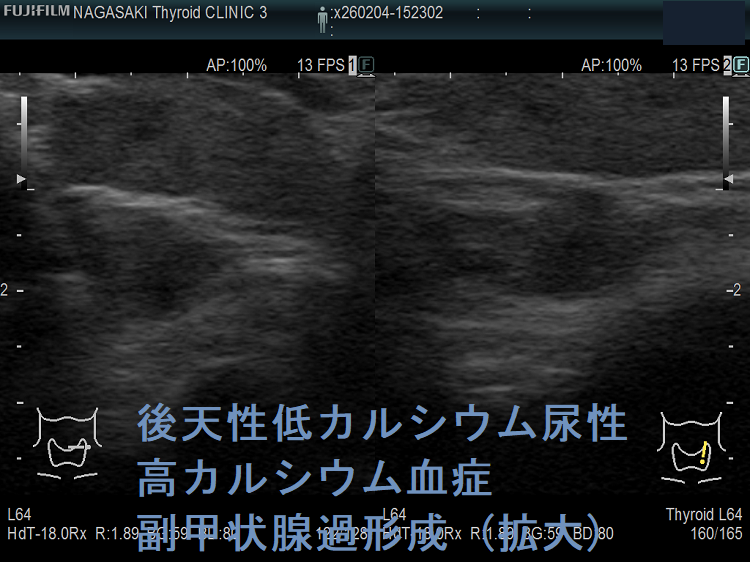

左は、隈病院の研究会資料から転載させていただきました。

下は、隈病院の研究会資料から転載させていただきました。